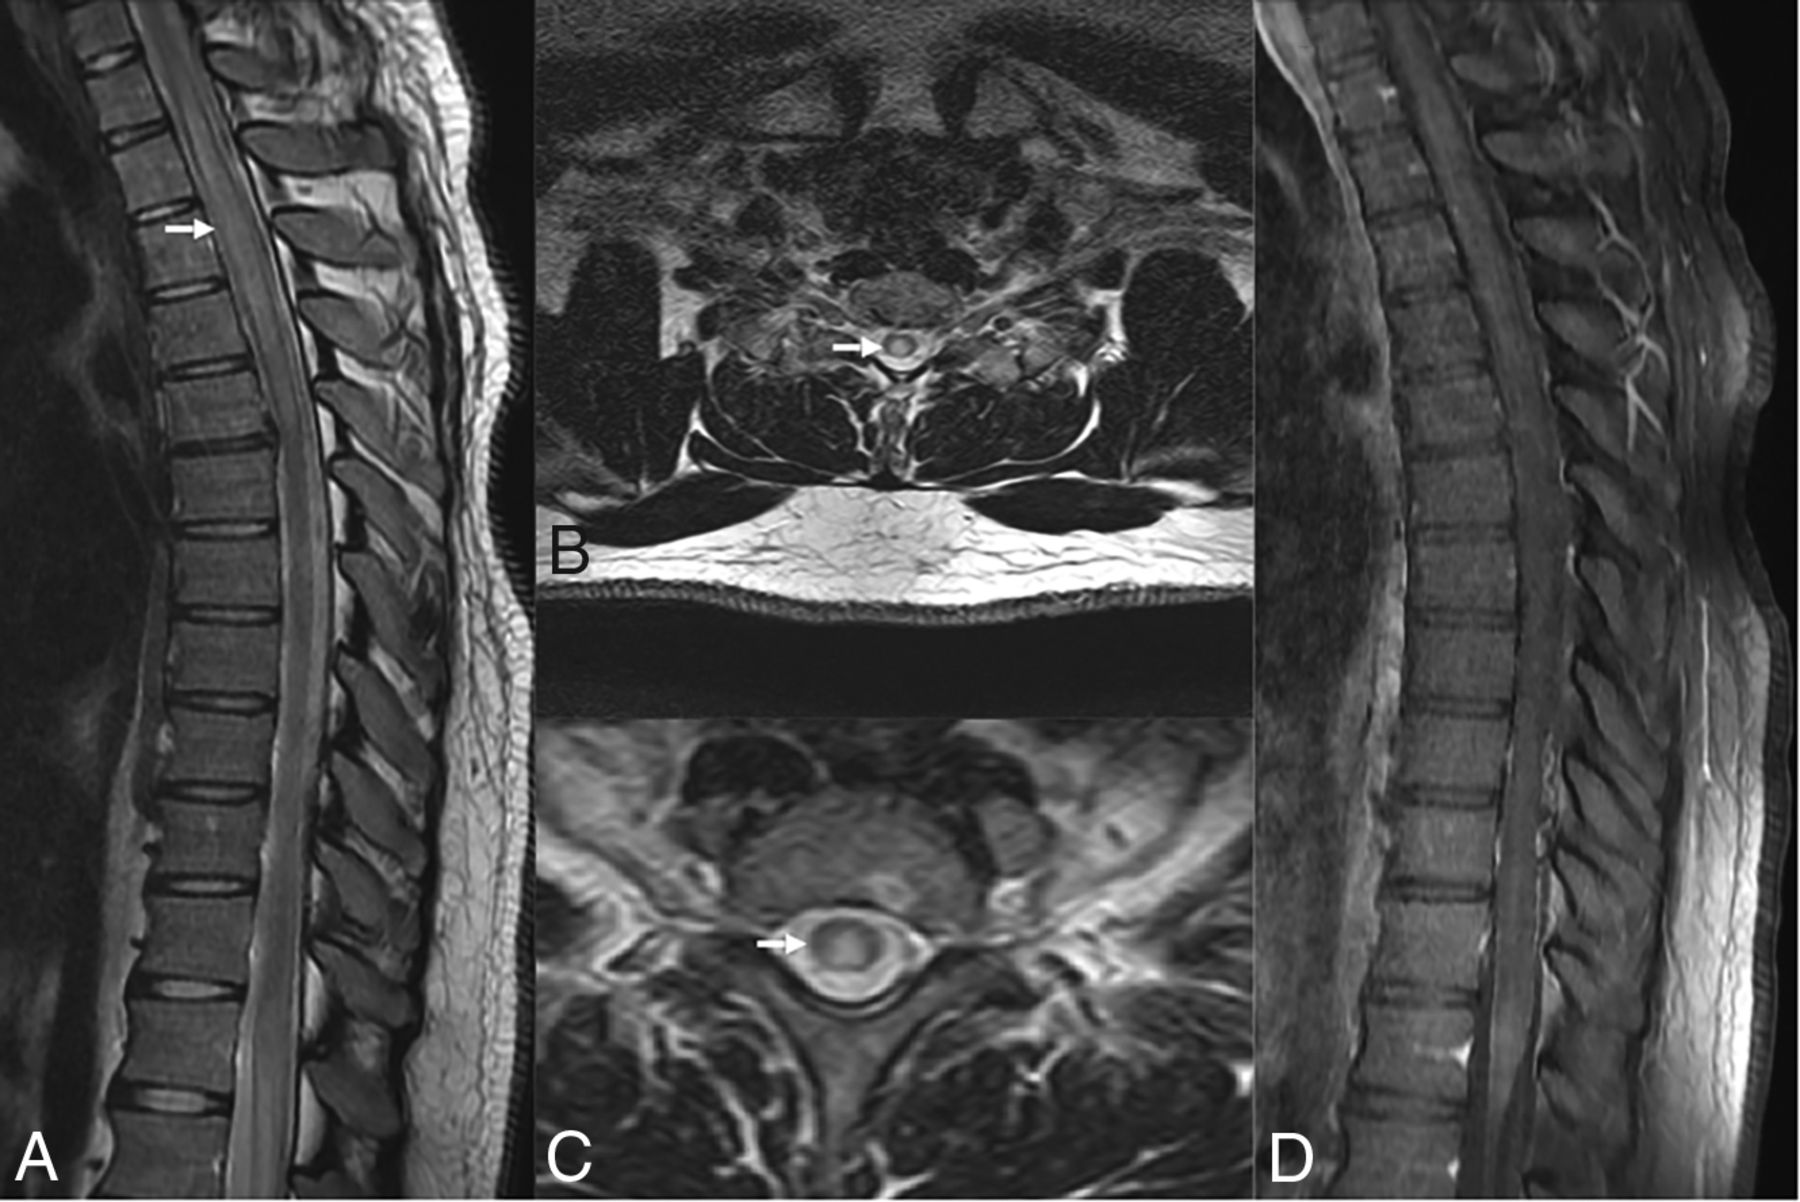

Under the World Health Organization Classification of Hematolymphoid Tumors (2022), LG is an LPD occurring exclusively in immunocompetent patients. Brain involvement is reported in up to 30% of patients with LG and is often secondary, with sporadic primary CNS involvement.49 Brain lesions may be diffusely infiltrating or masslike and show nodular, perivascular, or ringlike enhancement. Subependymal extension or leptomeningeal involvement may be present (Fig 4). LG typically exhibits an angiocentric and angiodestructive infiltrate consisting of lymphocytes, histiocytes, and sporadic plasma cells, with rare neutrophils and eosinophils. Necrosis may be observed in higher-grade lesions, while well-formed granulomas are not seen. The differential diagnosis for LG includes CNS lymphoma and vasculitis.50,51 Imaging findings are nonspecific and overlap with multiple tumoral and nontumoral pathologies, including glioblastoma, vasculitis, and chronic lymphocytic inflammation with pontine perivascular enhancement responsive to steroids (CLIPPERS).50⇓⇓⇓-54 Treatment options include observation, resection, chemoradiation, corticosteroids, interferon, immunoglobulin, and rituximab.54

EBV lymphomatoid granulomatosis. A 40-year-old man with a history of HIV. EBV lymphomatoid granulomatosis was the finding of a prior right thalamus biopsy. Lymphohistiocytic infiltrate was the finding of a biopsy, consistent with EBV-associated lymphoproliferative disorder. Coronal T1-weighted postcontrast images show linear and punctate enhancement foci in the left parieto-occipital lobes (arrow).